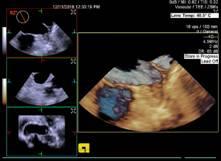

患者袁先生,有心脏二尖瓣及主动脉瓣杂音。心血管内科医生怀疑二尖瓣和主动脉瓣瓣膜病。12月5日早上,在超声室行局部麻醉下经食道四维超声心动图检查,清晰显示主动脉瓣重度狭窄,钙化呈功能二叶,排除了二尖瓣瓣膜病变,给临床提供了依据。

此项新技术的开展不仅能克服经胸的肺气、肥胖、胸廓畸形等因素的干扰,还可以更加直观全面准确的诊断疾病,是心脏超声诊断的“新武器”,大大提高了心脏方面的诊断水平。